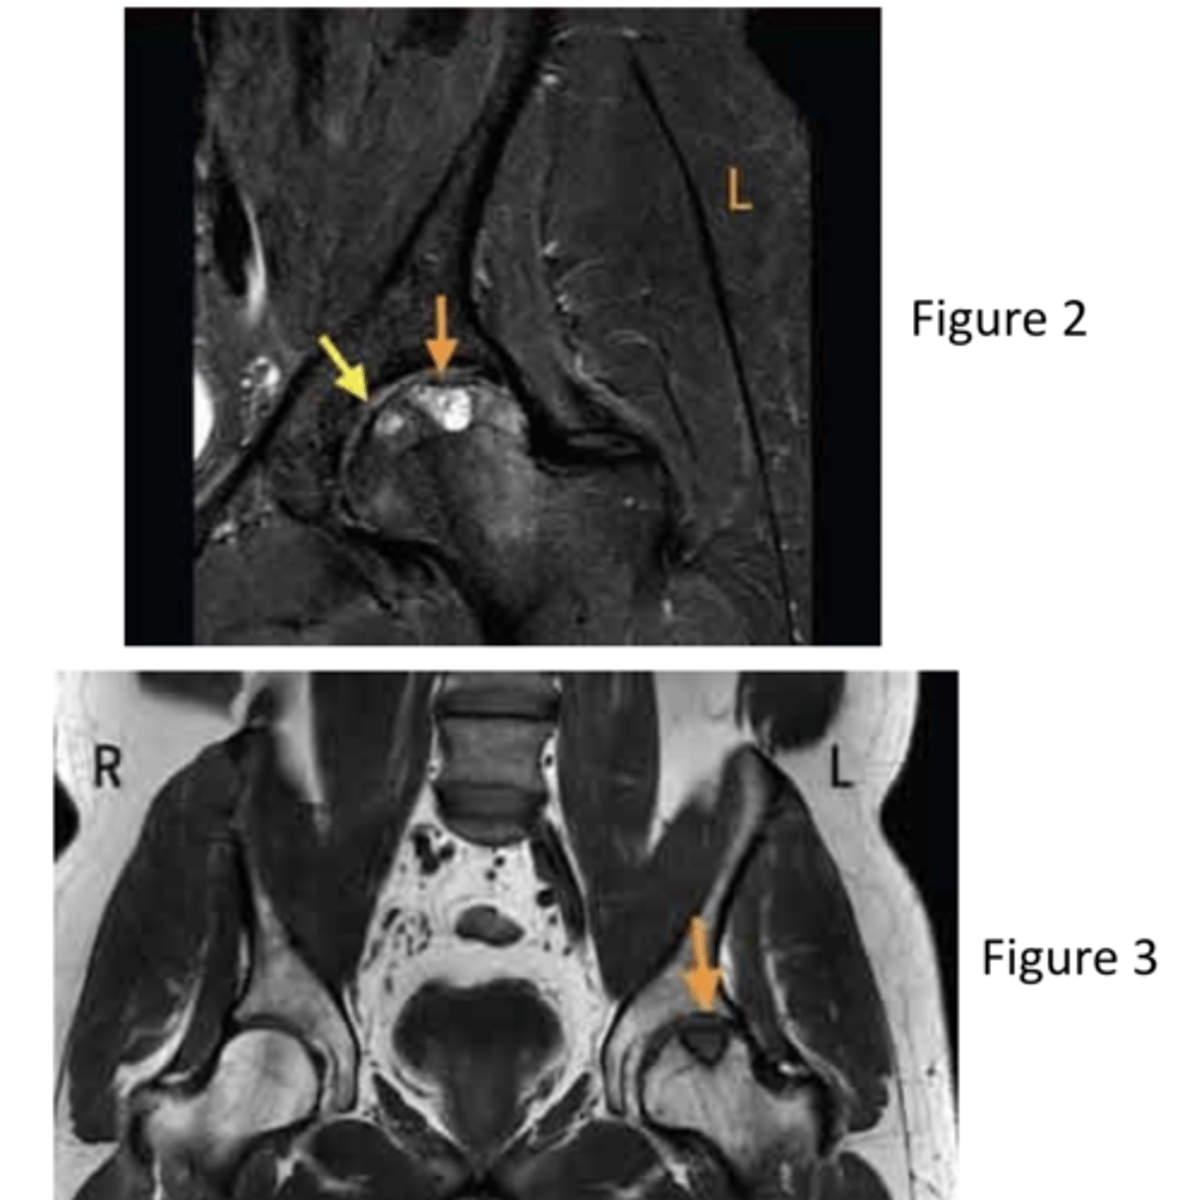

what are the MRI views of figure 2 and 3, respectively?

coronal and coronal

after revealing an osteochondral fracture of the left femoral head, what should the next steps be for the patient?

discuss with a surgeon for possible surgical options